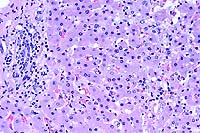

- Case 22-3. Spinal cord. Numerous punched out areas

represent necrosis and loss of white matter. Note the macrophages

in the center of the field (Gitter cells). There is a mild perivascular

infiltrate of lymphocytes.

- Case 22-3. Spinal cord. There is diffuse degeneration

and loss of myelin in axonal tracts (spongiosis). A single glial

cell in the center contains an eosinophilic intranuclear inclusion

(arrow).